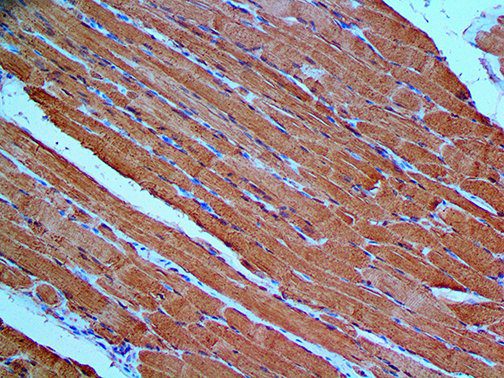

This activation induces inflammatory monocytes to highly express IL-6, starting a localized and then systemic cascade effect that results in hyperproduction of IL-6, which accelerates the inflammatory process. Because IL-6 also increases vascular permeability, excessive levels cause blood vessels to become very leaky. This, along with clotting factors released from vascular endothelial cells, stimulates the coagulation cascade, resulting in microthrombosis (tiny clots), which leads to ischemia and tissue death of the kidney, intestines, heart, liver, brain and extremities.